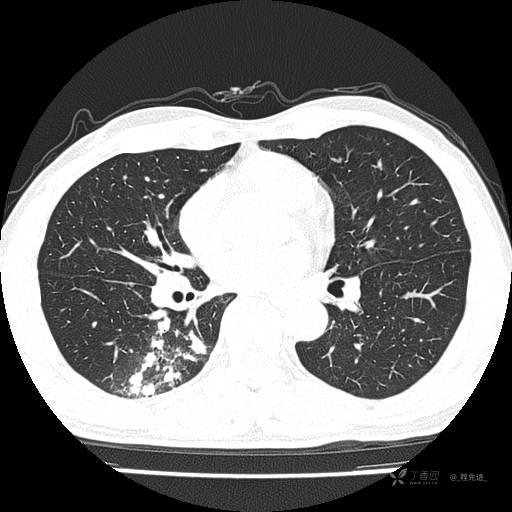

2月特别精彩病例|咳嗽、咳痰20余天,典型病例分享【结果已公布】

患者年龄:51岁

主诉:咳嗽、咳痰20余天

简要病史:20余天前开始出现咳嗽、咳痰症状,阵发性刺激性咳,白色粘痰,不易咳出,无发热,无咯血,无恶心、呕吐等不适,未诊治,咳嗽、咳痰症状持续存在。

体格检查:T:36.3 ℃ P:79 次/分 R:20 次/分 BP:128/64 mmHg,神志清楚,呼吸平稳,双肺呼吸音粗,右下肺闻及细湿性啰音。心率79次/分,节律整齐,各瓣膜听诊区未闻及病理性杂音。腹部未见异常,双下肢无水肿。

辅助检查:我院门诊胸部CT示:如下。心电图:窦性心律;正常心电图。